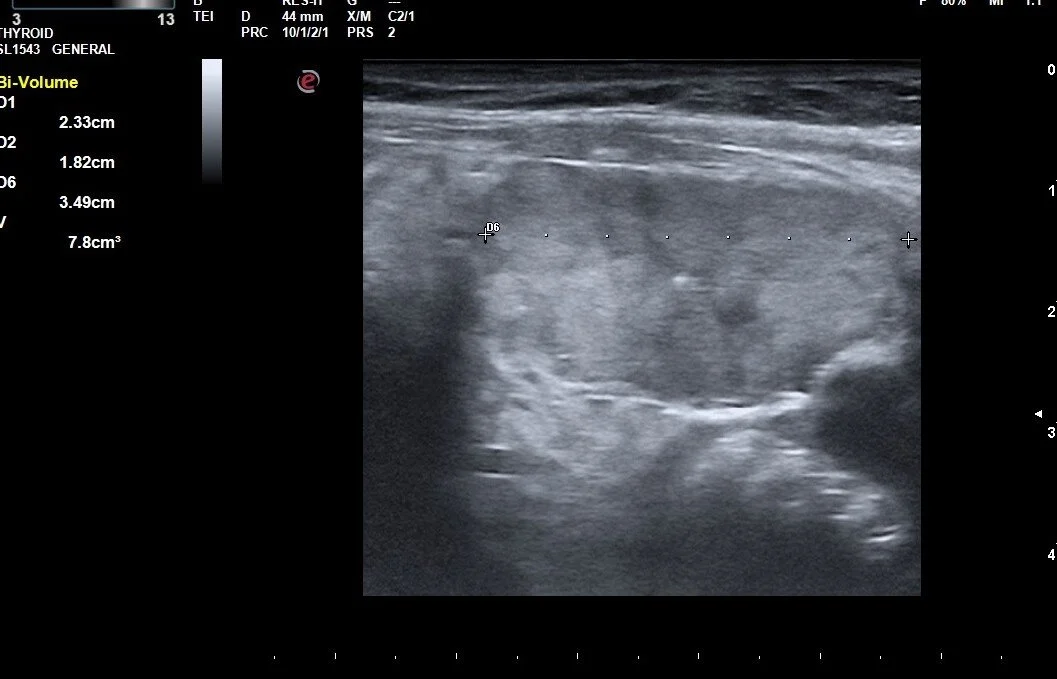

This case shows effect of 2 treatments on a large nodule and the correlation between volume reduction and normalization of thyroid levels

Ablation is accomplished by the dissipation of heat (produced by high-frequency radio waves) from the tip of a special water-cooled needle. Specialized white blood cells subsequently remove the dead nodule tissue in the weeks, and months following RFA, which causes the nodule to shrink considerably. Large-scale studies have shown an average reduction in nodule volume of approximately 60% after 3 months, and of 80% after one year, depending on the original nodule size and composition.

Most studies have suggested that nodules less than 10-12 mL in volume have a better chance of normalizing TFTs with 1 session of RFA